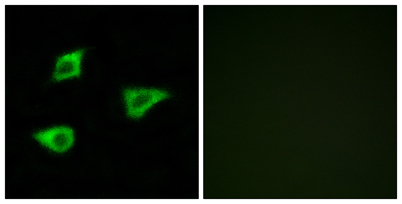

Product name: mAChR M4 rabbit pAb

Dilutions: Western Blot: 1/500 - 1/2000. Immunofluorescence: 1/200 - 1/1000. ELISA: 1/10000. Not yet tested in other applications.

Cellular localization: Cell membrane; Multi-pass membrane protein. Cell junction, synapse, postsynaptic cell membrane; Multi-pass membrane protein.